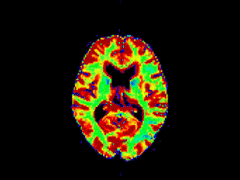

• Kontrastmittelgestützte Perfusionsbildgebung des Gehirns mittels MRT und CT.

• Entwicklung und Evaluierung neuer Berechnungsmethoden für PWI Parameterbilder.

• Volumetrische Auswertungen von PWI-Parameterbildern: "DWI - PWI Mismatch-Konzept".